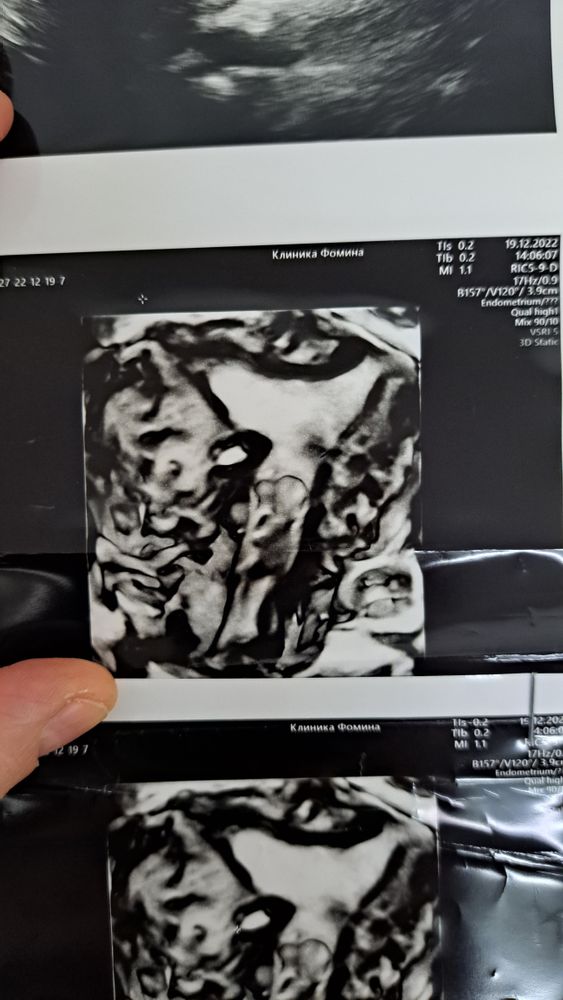

Арина, вот кстати фото 3д узи. Изображение Изображение Изображение Изображение Изображение в этом треугольнике серенькое - это эндометрий. и он однородный типа. справа кальценат. а вот блиде к шейке какая то фигня